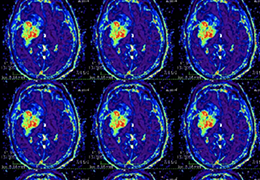

ART-Plan™ Artificial Intelligence Contouring